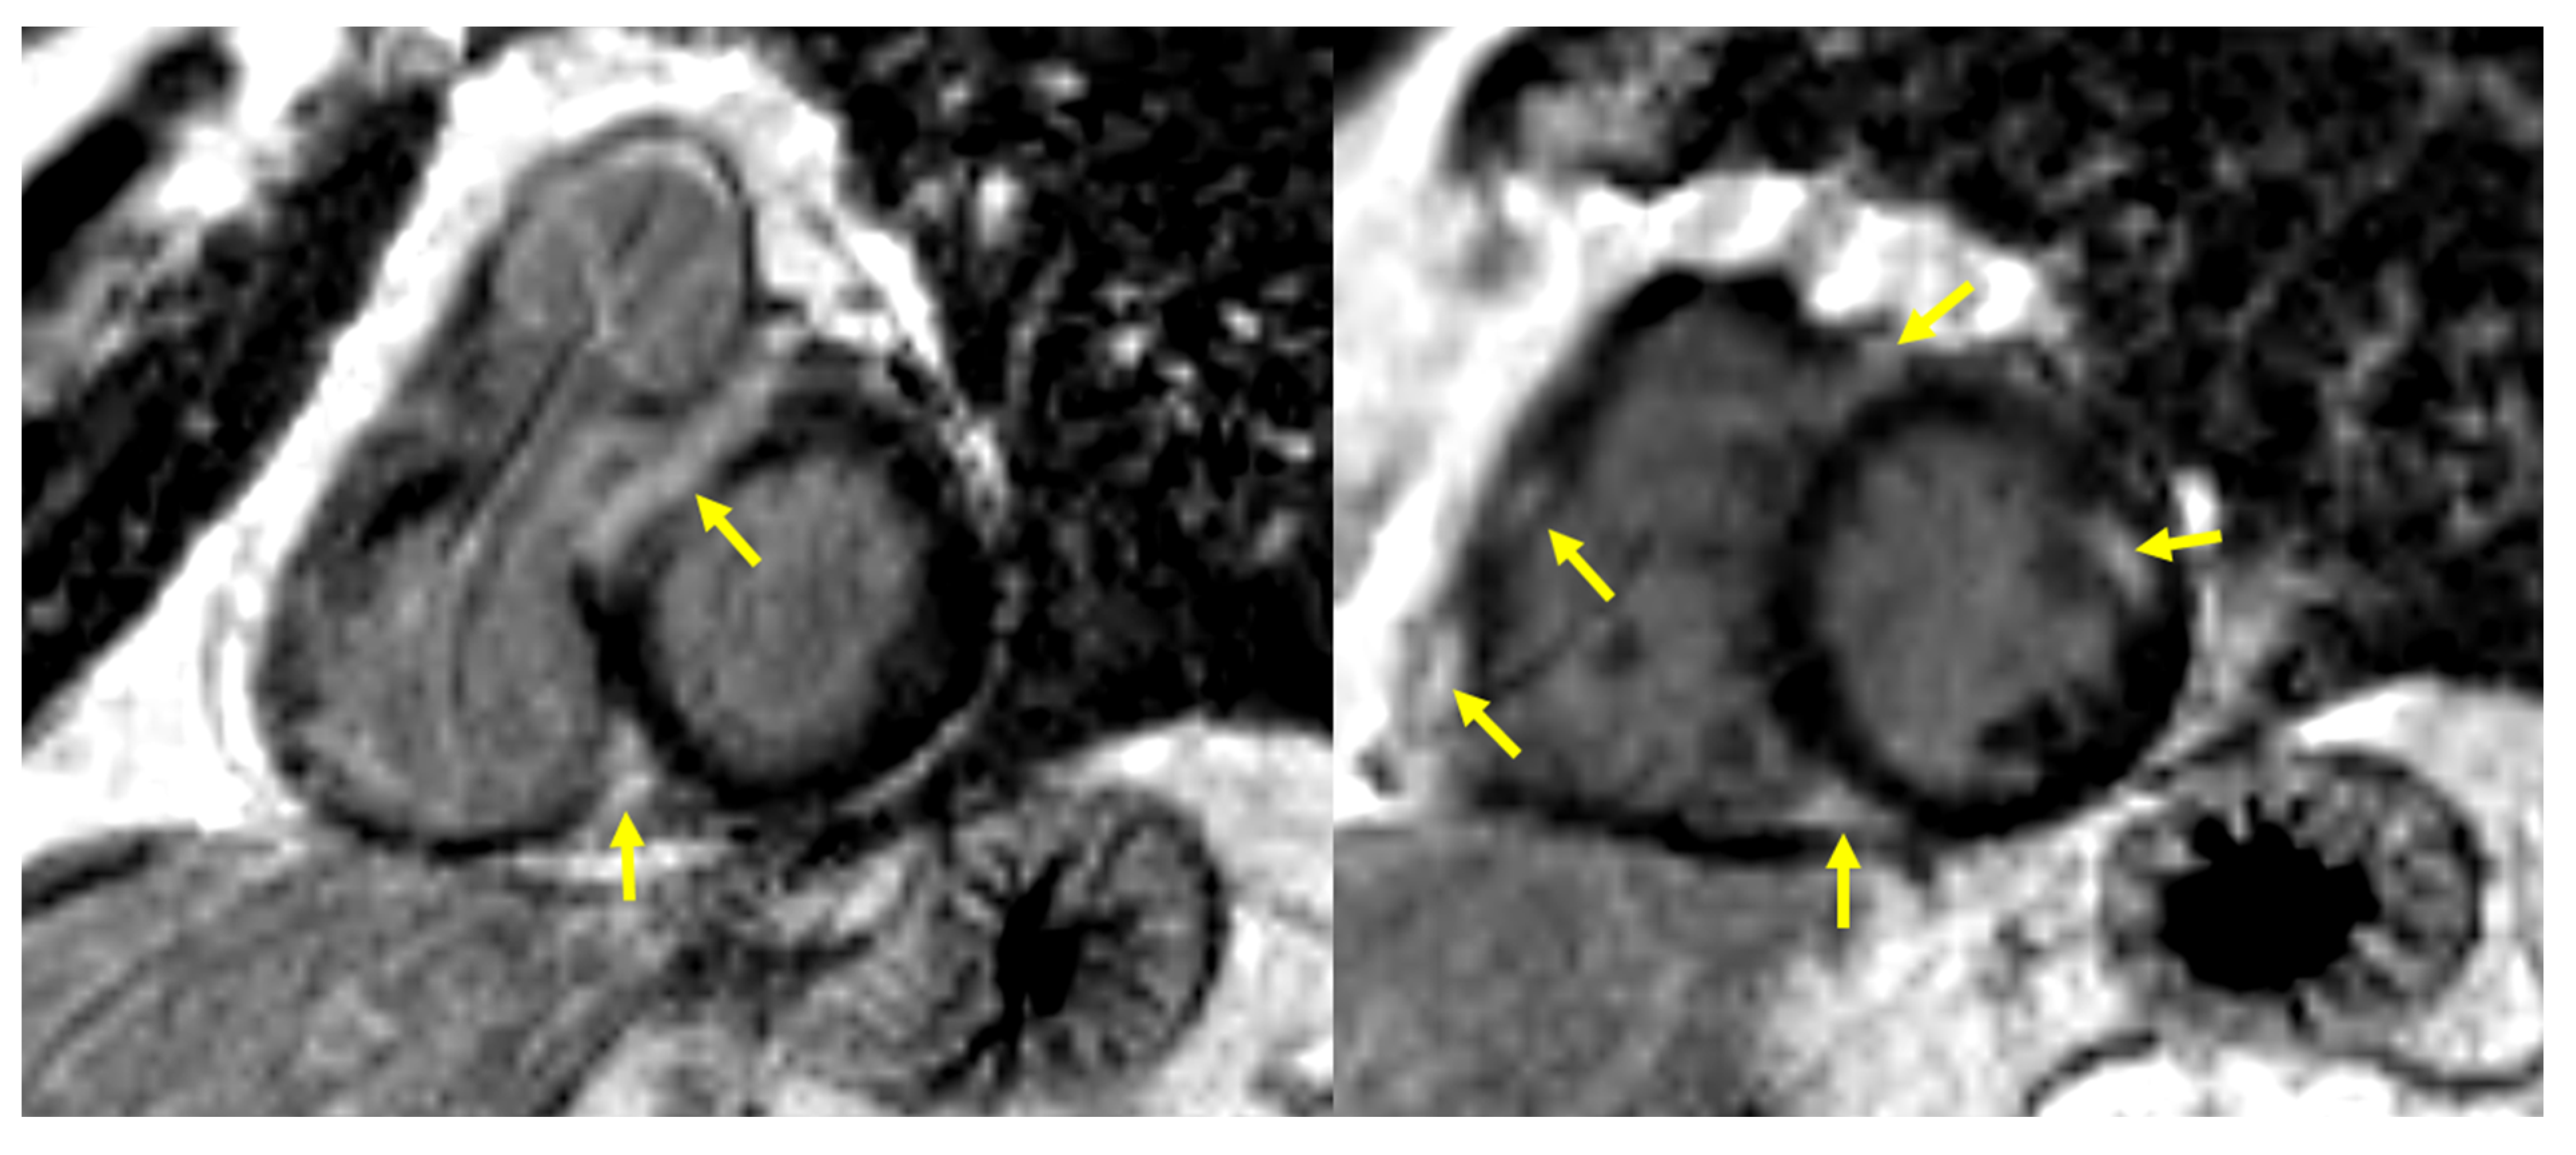

2. Materials and Methods

2.3. Screening and Diagnostic Procedures of CS